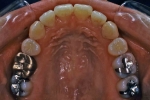

初診時